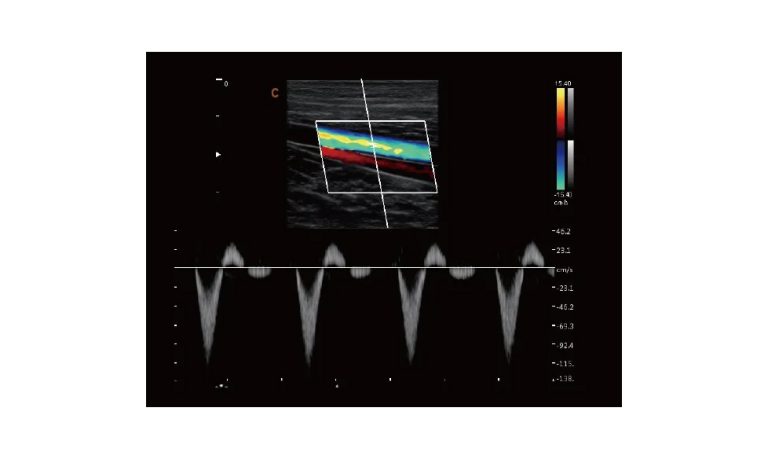

Ultrasound

Wide range of Ultrasound machines that suites a variety of applications from abdominal to rectal scans, we take in consideration how the world is moving towards mobility and mobile applications.

ECO5 VET

Ultra-Portable, Ultra- Affordable, Color doppler

The multi-purpose user presets, comprehensive measurement & report system, built-in EasyView image achieve system, quick image storage / retrieve / transfer, one-button direct print, make the complete workflow better than what you can dream of.